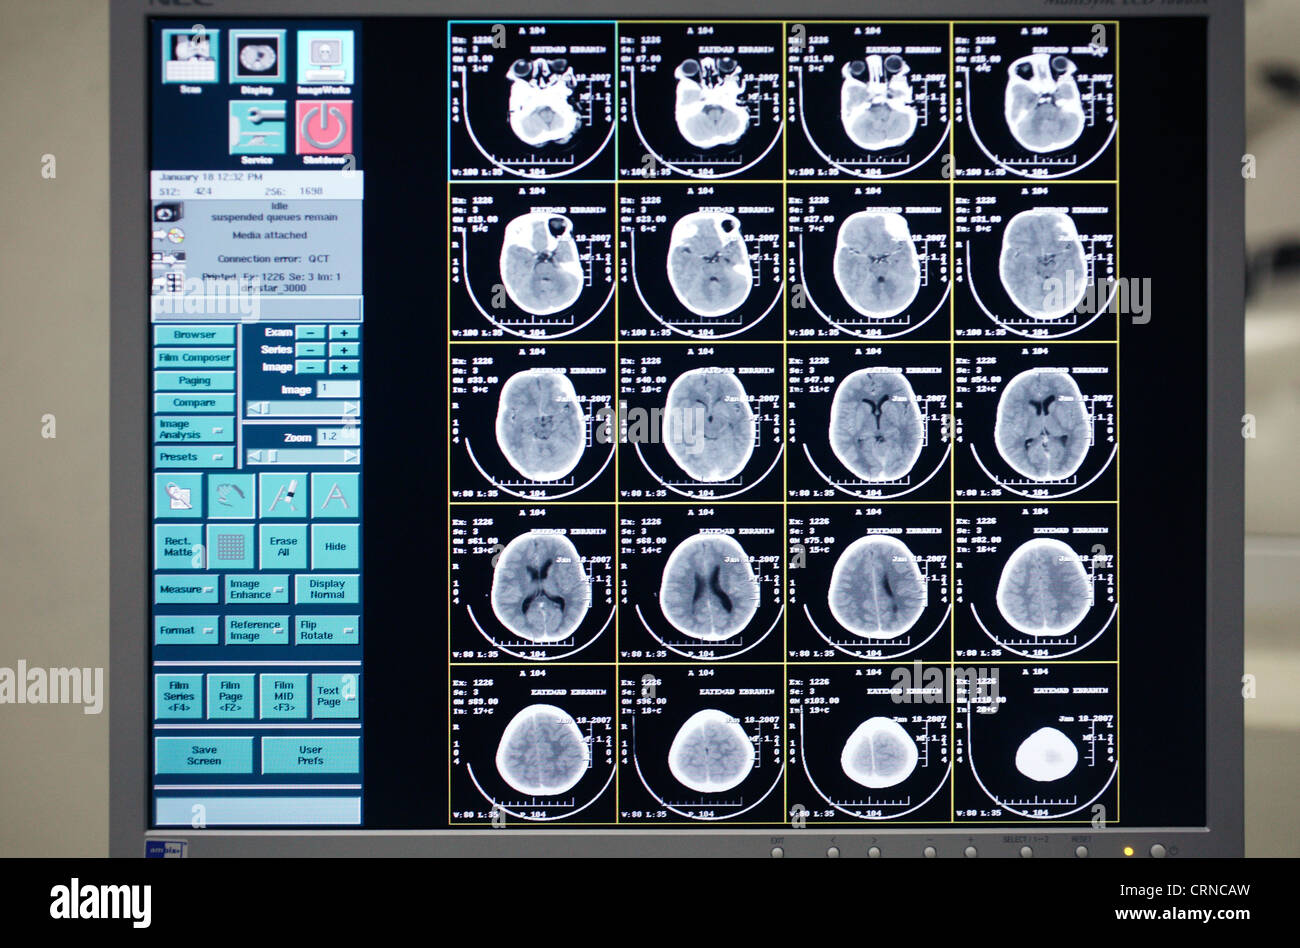

Sur l'image de l'écran d'un CT scan du cerveau d'un enfant de 5 ans souffrant de fibrose kystique. Banque D'Imageshttps://www.alamyimages.fr/image-license-details/?v=1https://www.alamyimages.fr/photo-image-sur-l-image-de-l-ecran-d-un-ct-scan-du-cerveau-d-un-enfant-de-5-ans-souffrant-de-fibrose-kystique-49028529.html

Sur l'image de l'écran d'un CT scan du cerveau d'un enfant de 5 ans souffrant de fibrose kystique. Banque D'Imageshttps://www.alamyimages.fr/image-license-details/?v=1https://www.alamyimages.fr/photo-image-sur-l-image-de-l-ecran-d-un-ct-scan-du-cerveau-d-un-enfant-de-5-ans-souffrant-de-fibrose-kystique-49028529.htmlRMCRNCAW–Sur l'image de l'écran d'un CT scan du cerveau d'un enfant de 5 ans souffrant de fibrose kystique.